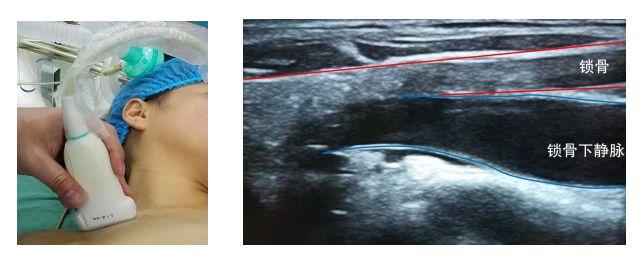

(二) 锁骨下静脉穿刺置管

超声引导锁骨下深静脉穿刺置管临床使用较少。具体方法参照传统经验性穿刺置管方法。

常规消毒铺巾、准备超声探头,使其平坦面接触皮肤,利用探头横向或纵向扫查血管走向,找到血管横截面(图7)或纵切面(图8),清楚探查到锁骨下静脉和动脉。仍需保证探头与穿刺针在同一平面,穿刺针在超声视野范围内。针尖进入血管后,回抽注射器,回血顺畅,穿刺针斜口完全位于锁骨下静脉,进一步常规置管固定。

图7 锁骨下静脉超声横截面二维图像

图8 锁骨下静脉超声纵切面二维图像